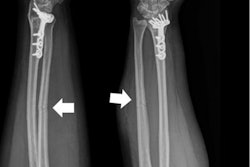

Ulna bone fractures, often referred to as nightstick fractures because they are seen in those who try to block blows from club-wielding police officers, occur when people hold up their hands to protect their faces from being struck. Researchers reviewed electronic medical records from six hospitals in search of isolated ulnar fractures in women between the ages of 18 and 50. Of the 62 patients identified, 12 were confirmed for intimate partner violence and another eight were suspected victims.

Analysis of the x-rays showed that minimally displaced fractures were linked strongly to intimate partner violence.

"The radiological characteristics we were looking at were the location of the fracture, the pattern of the fracture in terms of how it broke, and the displacement of the fracture," Sing said in a statement from the RSNA. "Out of all those things, what we usually saw was a minimally displaced fracture, meaning the bone is broken all the way through but has not shifted significantly."